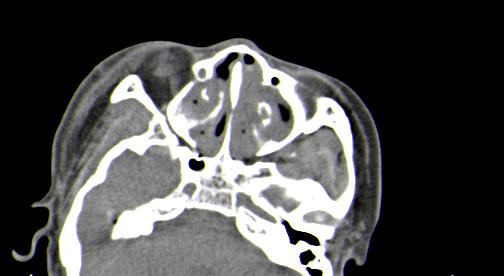

以下是引用皎皎白驹在2006-11-29 8:48:00的发言:[br]影像表现:双侧筛窦和上颌窦、鼻腔内均密度增高,右侧视神经增粗、弯曲,左筛窦顶部筛板及右侧纸板近视神经孔区可见骨折线。[br]结合临床表现考虑:右侧筛窦纸板近视神经孔区骨折致右侧视神经损伤。最好做个眼眶冠状扫描,更明确右侧视神经管是否狭窄。

以下是引用w_jianhua在2006-11-29 10:07:00的发言:[br]影像表现:双侧筛窦和上颌窦、鼻腔内均密度增高,右侧视神经增粗、弯曲,左筛窦顶部筛板及右侧纸板近视神经孔区可见骨折线。[br]结合临床表现考虑:右侧筛窦纸板近视神经孔区骨折致右侧视神经损伤。最好做个眼眶冠状扫描,更明确右侧视神经管是否狭窄。 [br] [br]支持[br]

以下是引用守望可可西里在2006-11-29 9:46:00的发言:[br][quote]以下是引用皎皎白驹在2006-11-29 8:48:00的发言:[br]影像表现:双侧筛窦和上颌窦、鼻腔内均密度增高,右侧视神经增粗、弯曲,左筛窦顶部筛板及右侧纸板近视神经孔区可见骨折线。[br]结合临床表现考虑:右侧筛窦纸板近视神经孔区骨折致右侧视神经损伤。最好做个眼眶冠状扫描,更明确右侧视神经管是否狭窄。